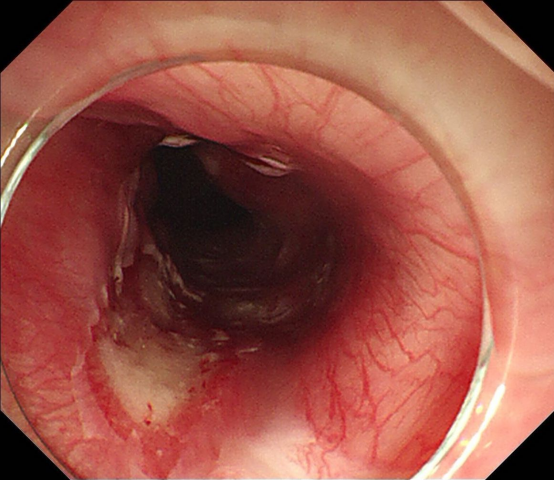

经过和患者及家属详细沟通后,胡兵教授团队制定了详细的手术方案,2025年1月15日,手术正式进行。在内镜引导下,胡兵教授利用高频电刀先切开病变基底部周边黏膜,进入黏膜下层,再逐步剥离病变基底部。由于病变太大,通过常规内镜下圈套器套住病变取出的方法力量太小,难以将病变全部取出,胡兵教授巧妙应用了外科手术中使用的卵圆钳将已经拖出体外的病变部分夹住后将全部病变顺利取出。40分钟后,胡兵教授完整切除了巨大包块,且术中出血量少(图1、图2、图3)。术后病变测量大小约22.0*5.5cm(图4)。病理检查显示为巨大纤维血管息肉。

(图1)